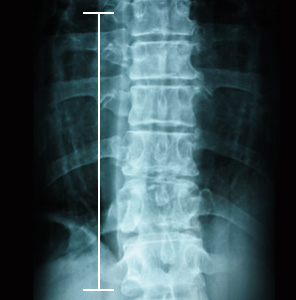

척추 측만증은 척추가 정면에서 보았을 때 옆으로 휜 것을 지칭하긴 하지만, 실제로는 단순한 2차원적인 기형이 아닌 척추 자체의 회전 변형과 동반되어 옆에서 보았을 때에도 정상적인 만곡 상태가 아닌 3차원적인 기형 상태를 말합니다. 검사는 방사선 촬영을 이용해 상담해드리고 있습니다.